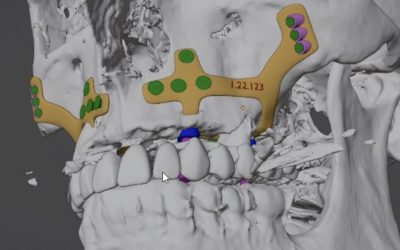

Con el advenimiento de nuevas técnicas, (implantes cigomáticos, pterigoideos, all on 4, implantes personalizados, implantes inclinados…etc.), cada vez nos decantamos más por evitar la utilización de injertos del propio paciente con el fin de evitar lesiones en la zona donante, reducir el número de intervenciones y el tiempo necesario para que el paciente lleve su dentadura fija de una forma satisfactoria.